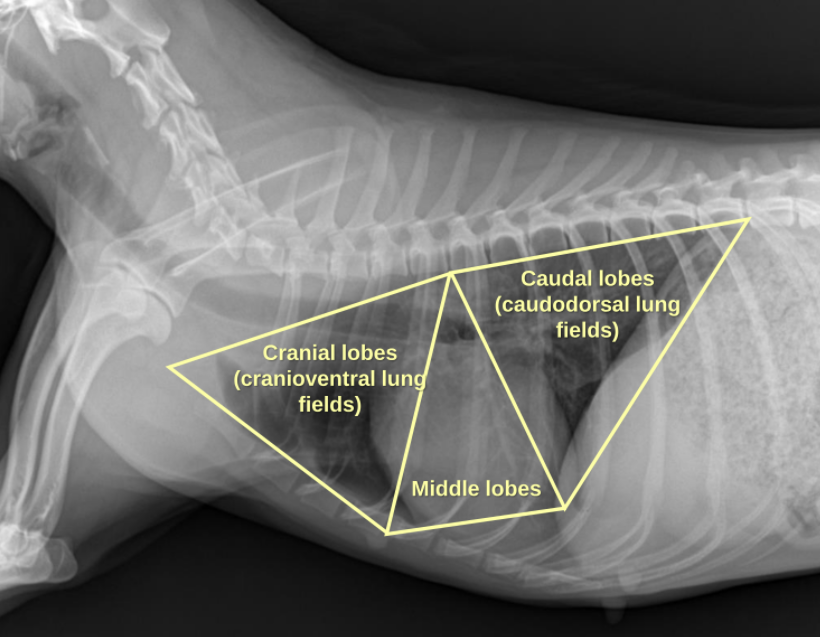

1. Normal Anatomy

| 정상적인 공기의 흐름 : Trachea - Bronchus - Bronchioles - Lung |